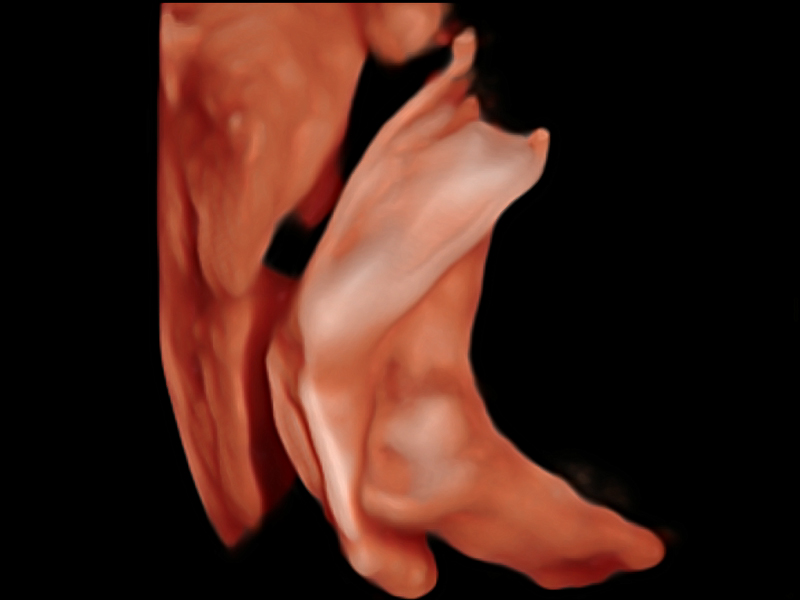

S-Fetus基于大數(shù)據(jù)深度學(xué)習(xí)算法,能夠幫助您在產(chǎn)前篩查過程中智能識(shí)別胎兒標(biāo)準(zhǔn)切面、自動(dòng)測(cè)量并錄入報(bào)告。一個(gè)按鍵,即可智能、精準(zhǔn)、高效地獲取胎兒生理指標(biāo),極大簡化您的產(chǎn)科檢查操作。

可快速對(duì)產(chǎn)科掃查切面完成胎兒生理學(xué)參數(shù)的自動(dòng)測(cè)量,減少操作者按鍵次數(shù),大幅提升檢查效率。

自動(dòng)識(shí)別頸項(xiàng)透明層并獲得NT值,為早孕胎兒畸形篩查提供有效測(cè)量工具,提高診斷效率和診斷信心。